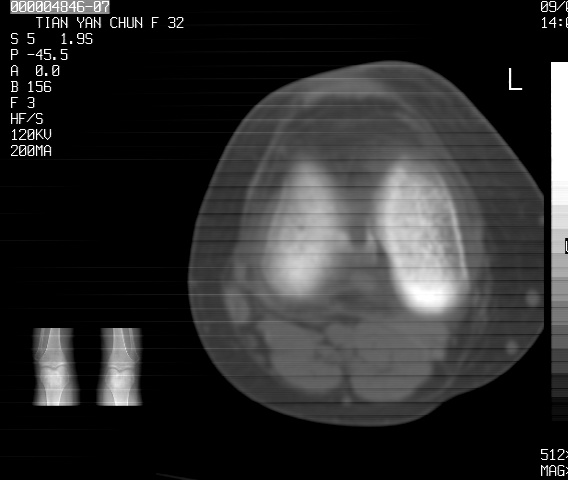

标题: CT18487:请会诊,女32岁,左膝疼痛数日 [打印本页]

标题: CT18487:请会诊,女32岁,左膝疼痛数日

关节面软骨有硬化环考虑退行性变

定位片可见髁间棘骨质增生,支持膝关节退行性变。

定位片可见髁间棘骨质增生,支持膝关节退行性变。建议mri 检查

考虑骨性关节炎